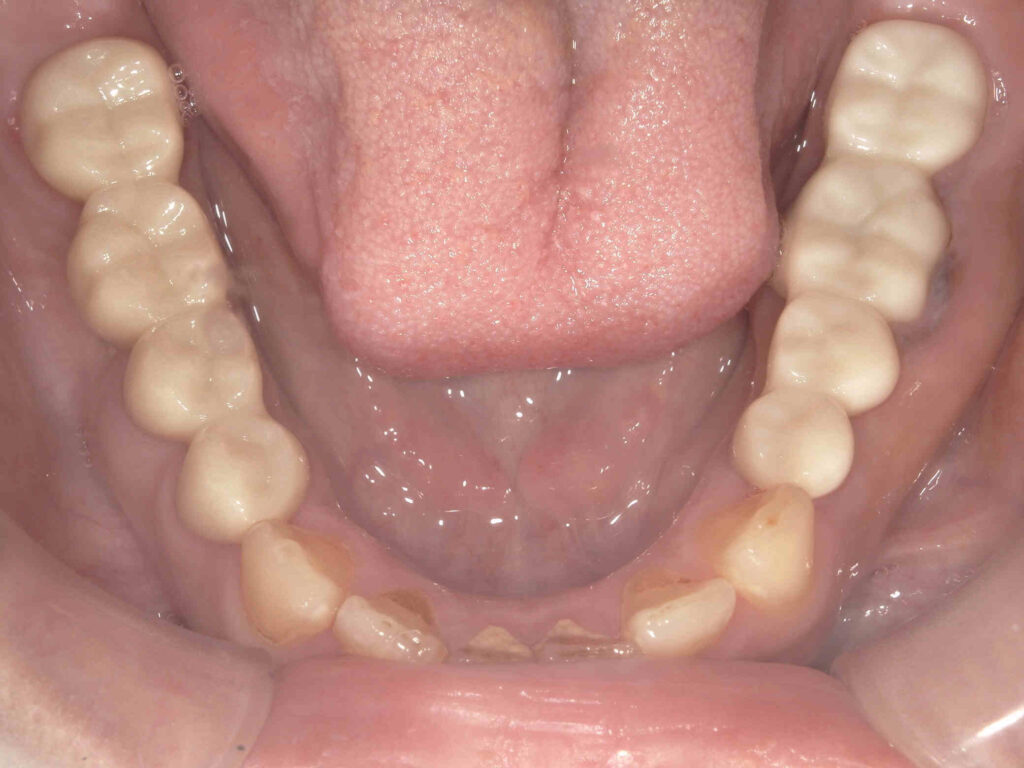

BEFORE

要抜去歯もありましたが、クラウンレングスニングにて保存を図りました。

AFTER

| 主訴 | 咬めない。歯を入れたい。 |

残根による咀嚼障害 |

| 治療内容 | フルジルコニアブリッジ (クラウンレングスニング併用) |

| 抜歯部位 | 左下5番 |

1年/15回 |

| 費用 | 616,000円 |